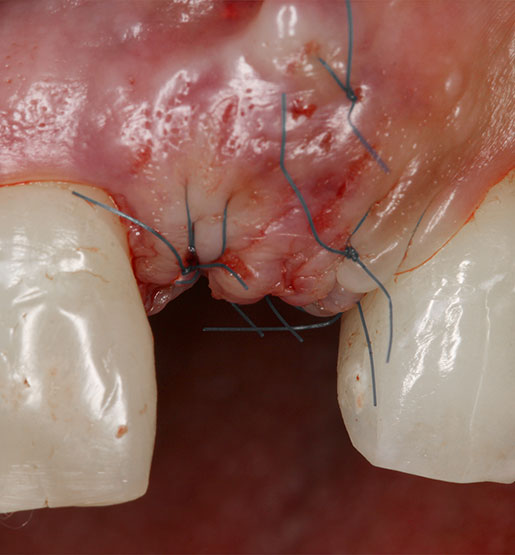

La cirugía periodontal consiste en eliminar por medio de un pequeño abordaje quirúrgico los defectos del hueso y la encía ocasionados por la periodontitis a través de los años.

Después de realizar el curetaje, las bolsas periodontales remanentes en la encía pueden volverse a infectar. Para evitar que esto suceda, se eliminan con una cirugía. En la intervención, las bolsas se retiran mediante la remoción del tejido blando enfermo y se corrigen los defectos del hueso con injertos óseos mediante una cirugía ósea o alguna técnica regenerativa.

Generalmente, las suturas se retiran una semana después de cirugía, sin embargo, si en la intervención se utiliza algún biomaterial como injerto de hueso, membrana o alloderm (matriz dérmica celular), la sutura que se emplea es distinta y tarda más en retirarse dependiendo de cada caso en particular.